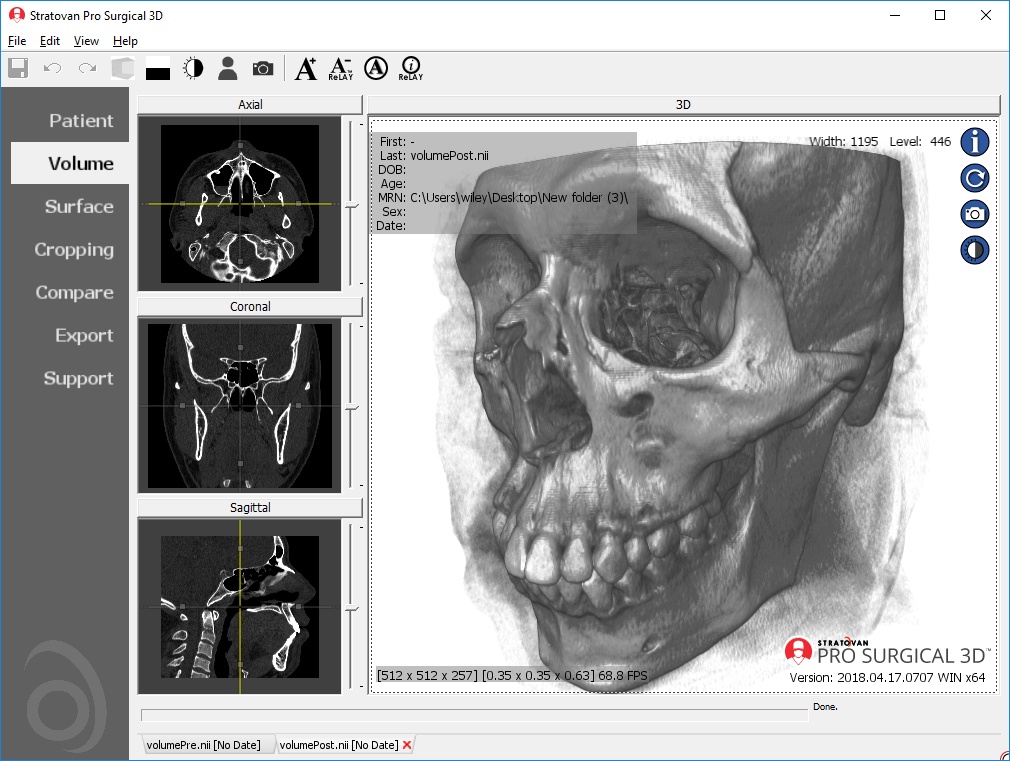

Лазерная камера для печати медицинских изображений на пленке стандарт dicom